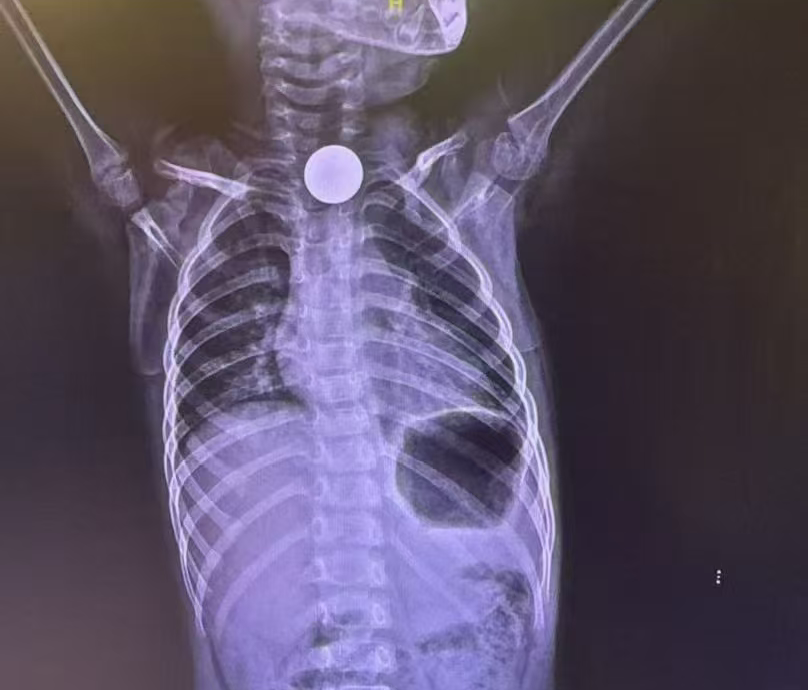

圆滑的钝形异物

如 硬币、玻璃珠 等,危险性相对较小,但如果是误吞入多枚 磁力珠,则十分 容易引起消化道梗阻、穿孔。

△卡在食道的硬币